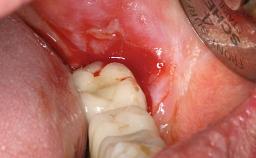

Retreatment of a Patient with Multiple Biological and Technical Complications and Failures

A 66-year-old patient presented because of retention loss of the tooth-supported FDP in the right maxilla (x-13-x-11). The mandibular full-arch implant-supported reconstruction (x-i34-i33-x-x-x-x-i43-i44-x) had suffered extreme wear. His medical history revealed high blood pressure, controlled with anti-hypertensive medication. The patient was a light smoker (2 to 3 cigarettes per day). The existing reconstructions had been performed alio loco about five years previously. That treatment had taken an extensive amount of time, and as early as during the fabrication of the reconstructions, multiple complications had occurred with the provisionals.

Periodontal Status History of periodontitis or genetic predisposition